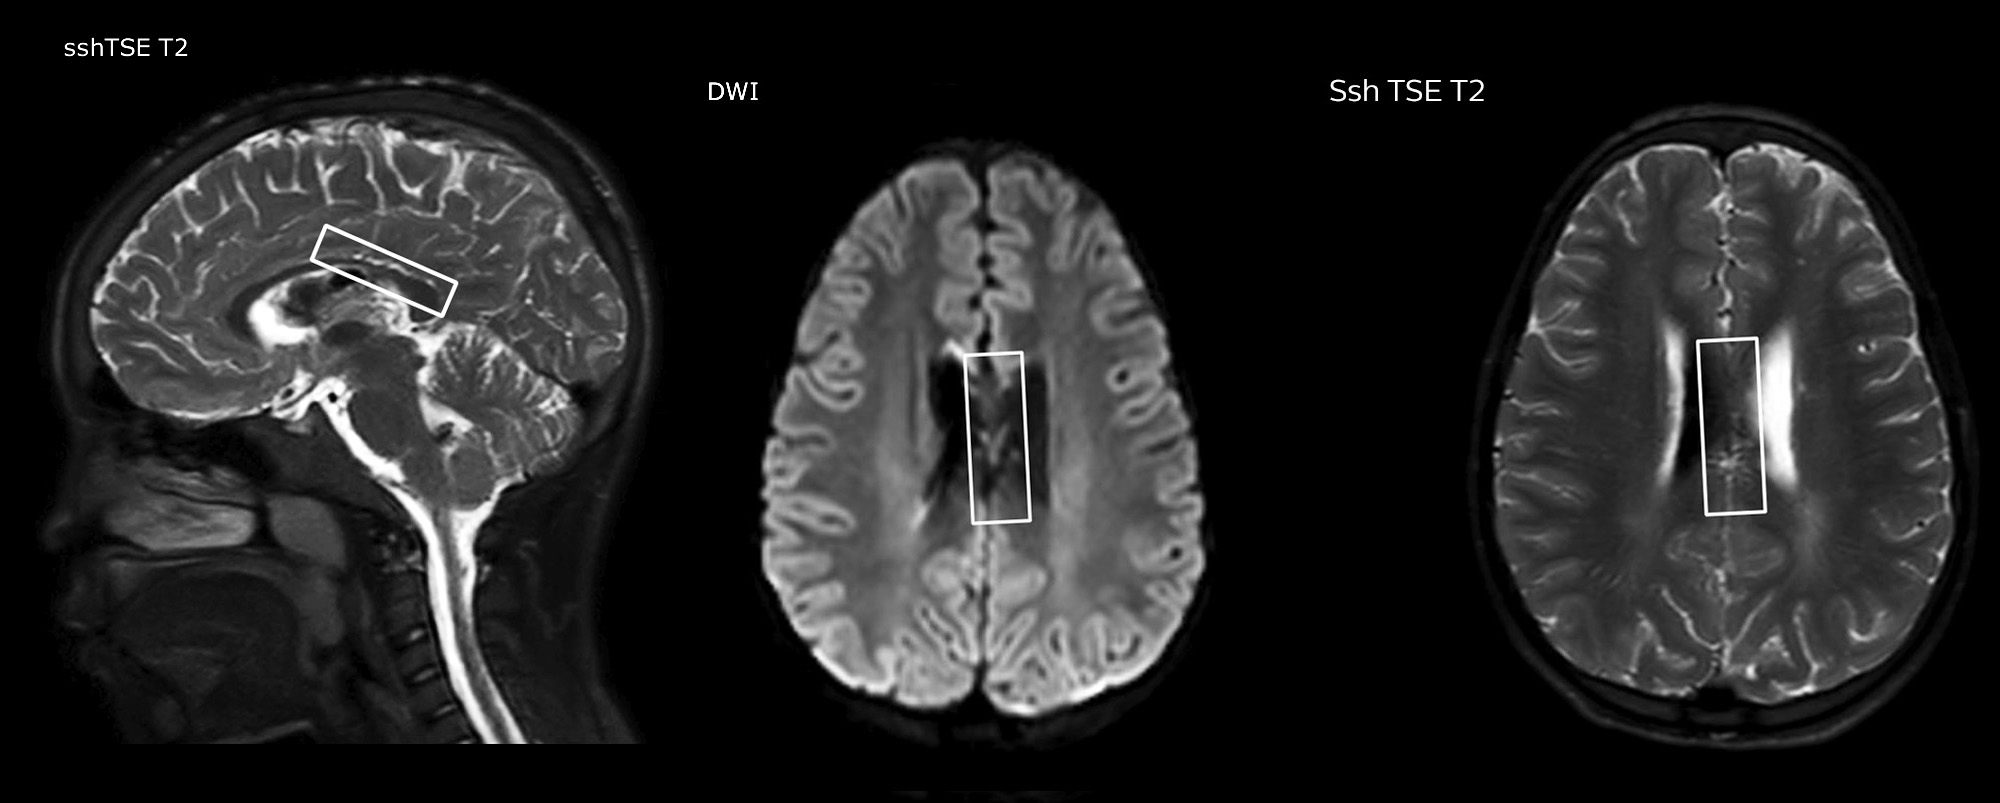

pCASL helps assess brain perfusion without contrast

Pseudo-continuous arterial spin labeling (pCASL) was developed for brain perfusion imaging without contrast agent. “This is very desirable in pediatric patients where the general trend is to limit the administration of contrast,” says Dr. Miller.

Dr. Miller uses pCASL for all patients who present with chronic and acute cerebrovascular abnormalities such as acute stroke, as well as patients who present with signs of acute inflammation in the brain, and occasionally in patients with tumors, to assess the perfusion status of their tumor.

“In combination with diffusion weighted imaging, it can help give a more extended assessment of the degree of perfusion abnormality in a patient who is suffering acute ischemia. We have a number of patients who have chronic arterial insufficiency due to prior arterial abnormalities or acquired arterial abnormalities such as sickle cell disease or neurofibromatosis. Sometimes the child’s first manifestation of disease progression is a reduction in brain perfusion before stroke symptoms manifest clinically or in diffusion weighted imaging. We use pCASL to help delineate the perfusion abnormality.”

Growing confidence in specific applications

“We built up confidence in pCASL by comparing it to contrast-based perfusion imaging. Once we had confidence that it was representing what the contrast perfusions were representing, we increased our diagnostic confidence by serial imaging in either the acute stage or the long term stages in a number of patients with arterial abnormalities.

To other new users I would recommend to also start to interpret the pCASL images in comparison with other standard imaging – T2 and FLAIR and DWI – until the user gains confidence in interpreting these images by themselves.”

“A powerful use of pCASL is in patients with chronic cerebrovascular stenosis, where clinicians desire information on how compensatory mechanisms of the brain are performing to enable perfusion to the brain. Often clinicians take into account how the compensatory mechanisms appear to help to provide adequate perfusion to the patient’s brain, and they may intervene surgically or make some other management decision.”

“Another special application is the assessment of cerebrovascular reactivity with a Diamox perfusion exam, where we subtract two sets of pCASL images.”

Efficiencies gained with pCASL

“pCASL has now become more of a first-line scan for assessing perfusion for us, as opposed to DSC-based perfusion imaging with contrast agent. And in patients who were not planned to have contrast, we can perform pCASL for perfusion imaging without need to stop the exam, pull the patient out, and put in an IV. It also negates the postprocessing that’s necessary for dynamic susceptibility contrasts. And it allows us to repeat perfusion imaging in the same patient at the same imaging time, which is helpful in terms of patient motion, or in a situation where a scan needs to be done before pharmacological perfusion imaging.”